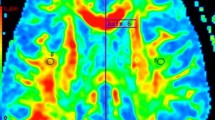

Compared with healthy controls, RRMS patients had significantly decreased DKI-derived kurtosis parameters in WM regions (P < 0.01, two-tailed, FWE corrected) with complex fiber arrangement, such as in the juxtacortical WM and corona radiata. DKI_MK, DKI_Ka and DKI_Kr could detect abnormal diffusion in 78.2%, 53.5% and 76.7% voxels of the whole WM skeleton respectively. Kurtosis parameters are shown in Fig. 1.

TBSS shows WM regions with significant differences in the DKI_MK, DKI_Ka and DKI_Kr between RRMS patients and healthy subjects (P < 0.01, FWE corrected). Green represents mean FA skeleton of all participants; blue represents reduction in RRMS patients. The percentage in the left column represents the percentage of the abnormal voxels relative to the whole skeleton voxels for each parameter